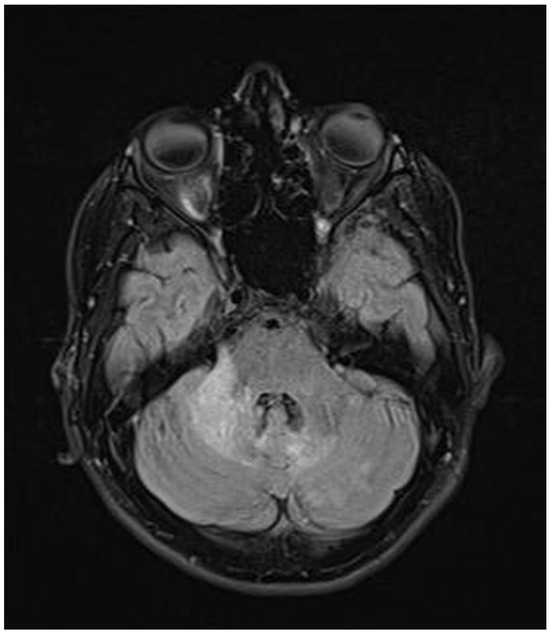

Figure 6.

Transverse FLAIR brain magnetic resonance image showing a subcortical demyelinating focus in the right frontal lobe (March 2022).

ADEM recurrence was recognized. The patient received immunoglobulins (2.0 g IV). After rehabilitation, an improvement in the neurological condition was observed over the next four weeks. The boy returned to school. Subsequently, he reported visual acuity disturbances in the left eye. Therefore, he was hospitalized in the neurology department. On admission, neurological examination showed horizontal nystagmus, lack of abduction in the right eye, dysarthric speech, and cerebellar syndrome. Brain MRI revealed numerous foci of increased signal on T2-weighted and FLAIR sequences, with the largest one occurring in the right cerebellar hemisphere accompanied by the involvement of the peduncle (Figure 5 and Figure 6) and bilateral involvement of the dentate nuclei of the cerebellum. Foci of increased signals on T2-weighted and FLAIR sequences were also found on MRI of the cervical and thoracic spine, meeting the LETM (longitudinally extensive transverse myelitis) criteria (Figure 7). Moreover, an orbital MRI showed “the left optic nerve was thickened to 3–4 mm, with increased T2 signal intensity indicating inflammation; the optic chiasm and right optic nerve were normal” (Figure 8). Again, positive serum anti-MOG antibodies were found in a clear titer of 1:100, while anti-AQP4 antibodies tested negative. Recurrent MOGAD was diagnosed based on the overall picture, and immunoglobulins were administered (a total dose of 2.0 g IV for five days). Oral azathioprine was included in the chronic treatment at a dose of 2 mg/kg body weight and oral methylprednisolone at a dose of 1 mg/kg body weight. After ten weeks (May 2022), right optic neuritis occurred during an attempt at withdrawing glucocorticosteroids. Methylprednisolone was reintroduced at a dose of 5 × 1.0 g intravenously. An MRI of the head revealed two new subcortical foci: one located in the right frontal lobe measuring 13 × 7 mm and another in the left parietal lobe measuring 19 × 14 mm (Figure 9). Additionally, the right optic nerve exhibited blurred outlines (Figure 10) and an increased signal in the central area, along with a marginally enhancing focus in the middle part of the right optic nerve measuring 2 mm in diameter. An ophthalmological consultation was conducted, revealing color vision deficiencies in the right eye across all axes, with no reading capability in the left eye. An OCT examination showed that the retinal nerve fiber layer (RNFL) in the right eye was normal (higher than a month earlier, suggesting a possible inflammatory process), while the left eye exhibited significantly reduced RNFL and ganglion cell count. Atrophy of the left optic nerve was diagnosed. Based on the clinical presentation, recurrent optic neuritis was diagnosed as a manifestation of another MOGAG, correlating with the onset of right optic neuritis following the discontinuation of methylprednisolone. Therefore, a decision was made to increase the dose of azathioprine to 2.5 mg/kg body weight and to maintain methylprednisolone for the following weeks. After the diagnosis of MOGAD with a typical radiological and clinical picture (ADEM, MDEM, recurrent ON) and the initiation of chronic immunosuppressive treatment, no more epileptic seizures were observed. It was decided to discontinue antiepileptic drugs, starting with gradual valproic acid.

Considering the criteria mentioned above, we focused on two demyelinating syndromes for differential diagnosis: multiple sclerosis and neuromyelitis optica spectrum disorder (NMOSD). To accurately diagnose demyelinating lesions, we conducted tests to detect antibodies against aquaporin-4 (AQP4) and myelin oligodendrocyte glycoprotein (anti-MOG), following the established gold standard [9]. In addition to the positive/clear titer of anti-MOG antibodies and the exclusion of antibodies against AQP4, imaging tests—resonance imaging (MRI) of the head and spinal cord—help make the diagnosis. Unlike MS, magnetic resonance imaging of the brain reveals lesions with unclear boundaries, more often located subcortically, with a characteristic cloud-like shape and a particular location in the cerebellar peduncles [1,5,10,23]. MOGAD lesions are extensive, often bilateral, and located in the thalamus and basal ganglia [1,23]. In NMOSD, brain lesions are more often located near the third ventricle [5]; the involvement of the area postrema is particularly characteristic, and the lesions usually surround the lateral ventricles [5,6].